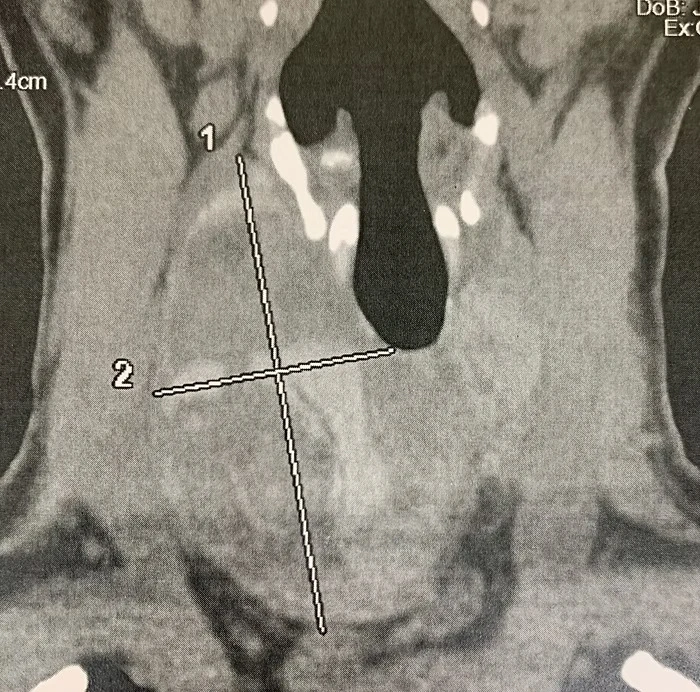

Case of a 37 years old Woman with 7cm Right Ishmic Nodes of the Thyroid Gland. Right Lobo-Isthmectomy was performed with the TOETVA procedure allowing no scar in neck.